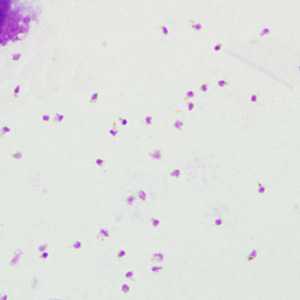

Wright-Giemsa stained blood smears and EDTA blood were sent for confirmatory diagnosis to the CDC from a Public Health Laboratory. The specimens were from a 46-year-old woman, but no travel history was available.